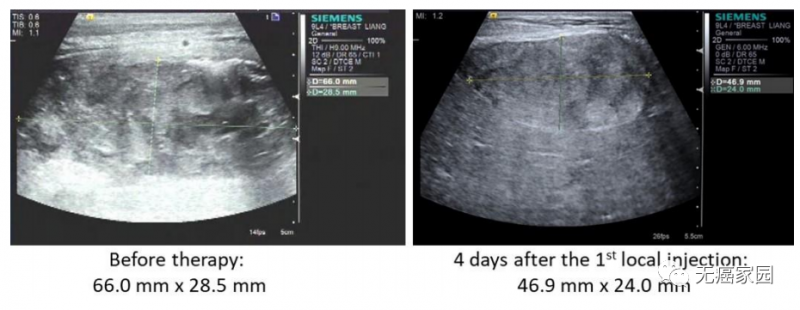

本研究中,采用局部输注 NKG2Dp CAR-NK的方式治疗了3 例转移性结直肠癌患者。前两例患者腹腔输注低剂量 CAR-NK 细胞后,可观察看腹水生成量减慢以及腹水样本中肿瘤细胞的数量急剧减少。第三例肝转移瘤患者采用超声引导下瘤内经皮注射和腹腔内灌注方式输注 CAR-NK细胞后,多普勒超声可见肝部肿瘤快速缩小,正电子发射断层扫描(PET-CT)提示经治疗的肝病灶为完全代谢反应。3 例患者在治疗过程中均无出现3级或以上的不良事件。

第3例患者多普勒超声成像显示局部注射 CAR-NK 细胞降低肝转移病灶肿瘤负荷

CAR-NK 细胞治疗后肝转移病灶 PEC-CT 结果对比图

(患者肝Ⅵ段的最大氟脱氧葡萄糖(FDG)摄取值从 8.2 降至 0.14,经评估为完全代谢缓解)